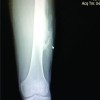

The proximal tibia was thickened and broadened. The medial and lateral joint lines were tender. He had diffuse swelling over the left knee and fixed flexion deformity of 5°. He was able further flex the knee up to 70°. His quadriceps and calf muscles were wasted (Fig. 1b and c). Radiographs (Fig. 2a and b) showed extensive degenerative change at the knee with a large, multilocular expanding lytic lesion involving the epiphyseal and metaphysical regions of proximal tibia. In some areas, the cortical margin was interrupted. Because of the aggressive appearance of this lesion, magnetic resonance imaging (MRI) with computed tomography (CT) screening was performed.